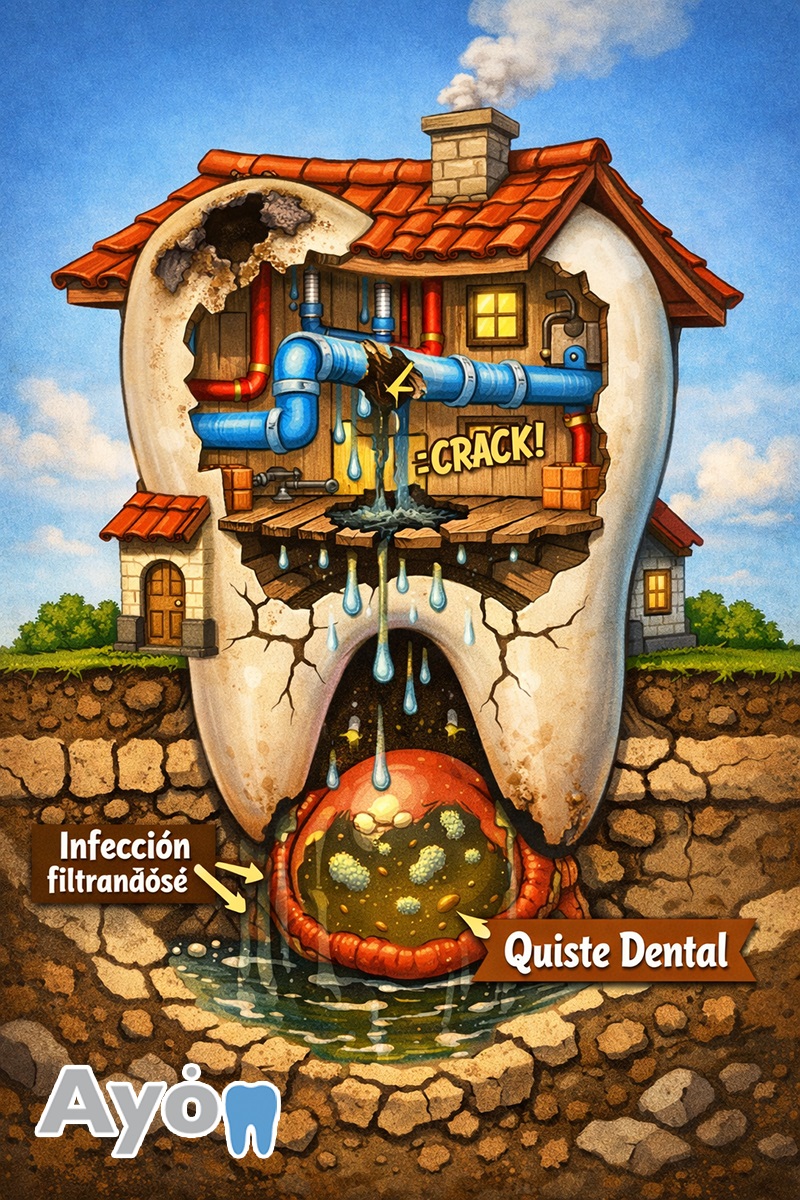

Imagina que tu diente es una casa. Por dentro tiene tuberías (los nervios). Si esa tubería se rompe (por una caries muy profunda o un golpe) y no se arregla a tiempo, el agua (infección) empieza a filtrarse por los cimientos.

El cuerpo, para defenderse, crea una burbuja en el hueso para encerrar esa infección. Esa burbuja es el quiste.

Porque aunque no duela, esa burbuja va creciendo poquito a poquito y come el hueso. Si dejamos que crezca demasiado, luego no hay suficiente hueso para poner un implante dental en Puebla o salvar el diente de al lado.

No es magia. Se limpia la tubería rota (tratamiento de conducto) o, si el daño es muy grande, se limpia directamente el hueso con una pequeña cirugía.